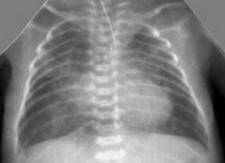

Снижение пневматизации легких, воздушные бронхограммы, границы сердца на рентгенограмме ещё различимы (Рис.5).

Рисунок 5. РДС. Рентгенограмма в прямой проекции, в горизонтальном положении. Верхние доли легких и средняя доля справа неоднородно слабоинтенсивно затемнены, корни легких расширены, не структурны. Сосудисто-интерстициальный рисунок легких деформирован, усилен, размыт. Тень средостения с нечётким контуром, протекционно смещена влево за счёт подворота. (Диагностика и лечение РДС недоношенных // метод. рекомендация, 2007)